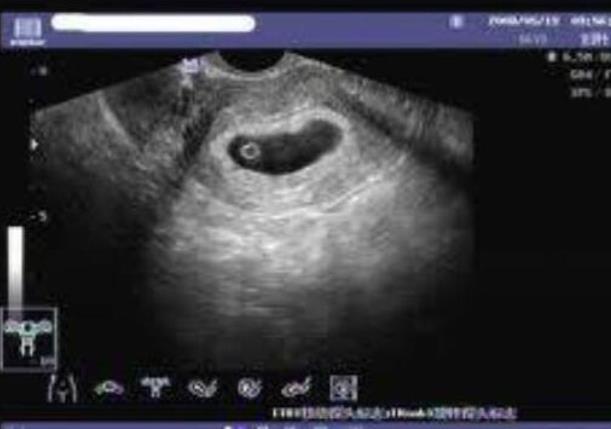

试管婴儿等到受精卵放入子宫里面之后就需要保胎了,但也不是随意的打黄体酮的,也需要看胎儿的发育情况来决定,如果一切正常就不需要打针。因为有的试管妈妈在怀孕的早期会有少量出血的症状,这个时候胚胎并不稳定,比如妈妈身体内的孕酮很低,那么就需要打黄体酮来保胎了。试管妈妈除了药物保胎之外,同时还需要注意作息时间,前三个月一定要多休息,重体力活是肯定不能做的,精神也不要太紧张。